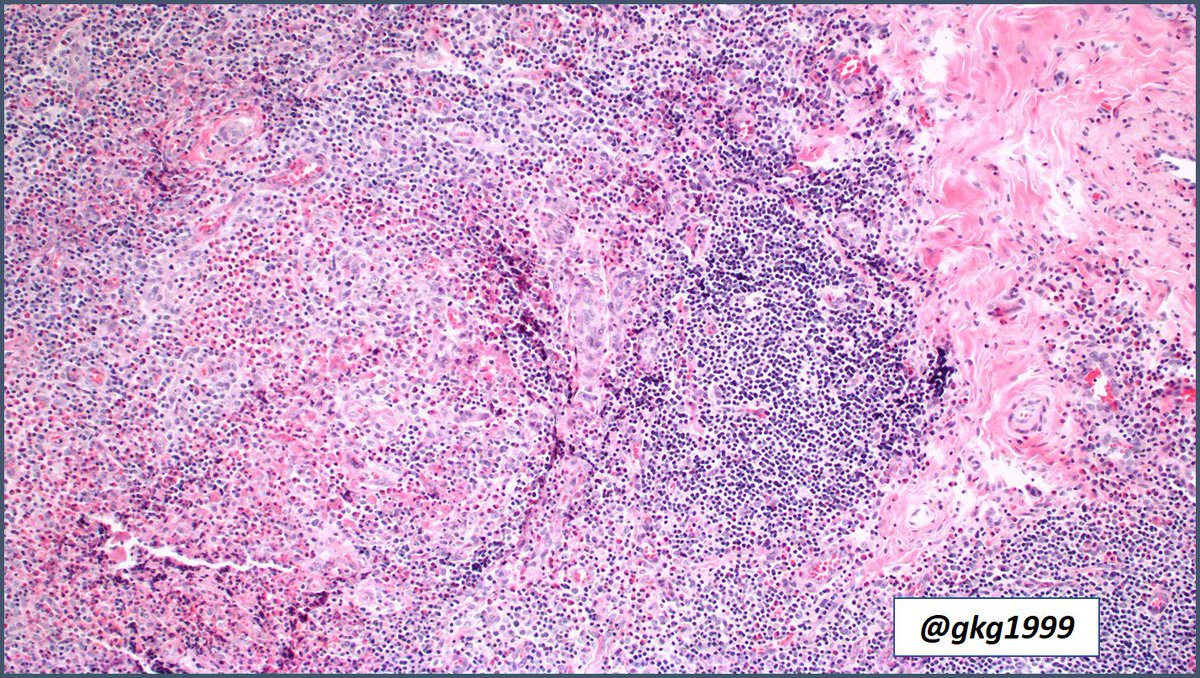

Kimura disease, Warthin-Finkeldey Cells #pathology #pathologists #hemepath #pathboards